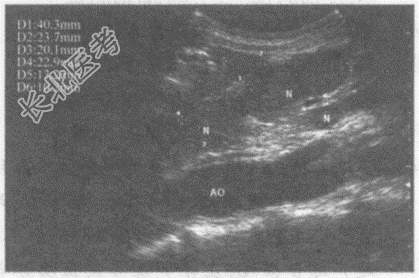

- 单项选择题临床资料:男性患者, 50岁,肺癌术后肝转移。

超声综合描述: 腹主动脉前方可见多个大小不等低回声,最大4.0cm×2.3cm, 边界尚清晰,形态不规则, 部分相互融合。

超声提示: A、腹腔多发肿大淋巴结(淋巴结转移癌)